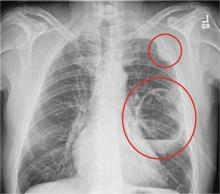

A 65-year-old man is transported to your emergency department from a local rehabilitation hospital. He is three weeks status post cardiac bypass surgery as well as “some other valve procedure.” In the past two to three days, staff members report, the patient has been less active and has not participated in therapy. This morning, he was found to be lethargic, and that is what prompted the call to 911. Examination reveals a lethargic male who has little verbal communication beyond moaning and groaning. His vital signs include a temperature of 36°C; blood pressure, 90/40 mm Hg; and heart rate, 135 beats/min. His O2 saturation is 90% on room air. Inspection of the patient’s chest reveals a recent, healing midline sternotomy incision. There is no overt redness or swelling. On auscultation, you note decreased breath sounds on the left side, with some coarse crackles. As you initiate your facility’s sepsis protocol order set, a stat portable chest radiograph is obtained. What is your impression?

The radiograph shows a large cavitary lesion within the left mid-lung with evidence of an air fluid level. This finding is strongly suggestive of a postoperative abscess or empyema. Secondarily, there is some pleural thickening within the left lateral apex region. This can be suggestive of scarring or possibly a neoplasm.

The patient was admitted to the ICU for a sepsis workup, and Interventional Radiology was consulted to evaluate for CT-guided drain placement.